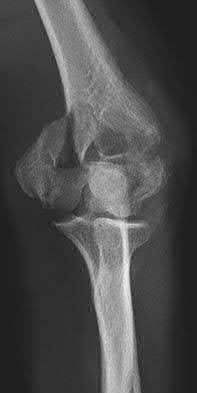

3. # Which of the following is not an appropriate implant for treatment of the fracture seen in Figure A?

5. Sliding hip screw Corrent answer: 5

The image shows a reverse obliquity intertrochanteric hip fracture.

According to the referenced article by Haidukewych et al, unstable peritrochanteric hip fractures have a worse outcome (failed in 9/16 cases) if treated with a sliding hip screw. Two additional factors that were found to have a strong correlation with postoperative failure (nonunion, loss of reduction) were poor reduction and poor implant placement. In this study, fixed angle devices were superior. Intramedullary fixation has the added advantage of a shorter lever arm and less potential for fracture collapse and limb shortening.

The IMN also acts as a medial buttress.

According to Sanders et al, the dynamic condylar screw (DCS) can also be used in subtrochanteric models, but should not be used if extensive comminution is seen, as they reported a high failure rate with DCS in these fractures if highly comminuted. They report a 77% overall union rate with this device.